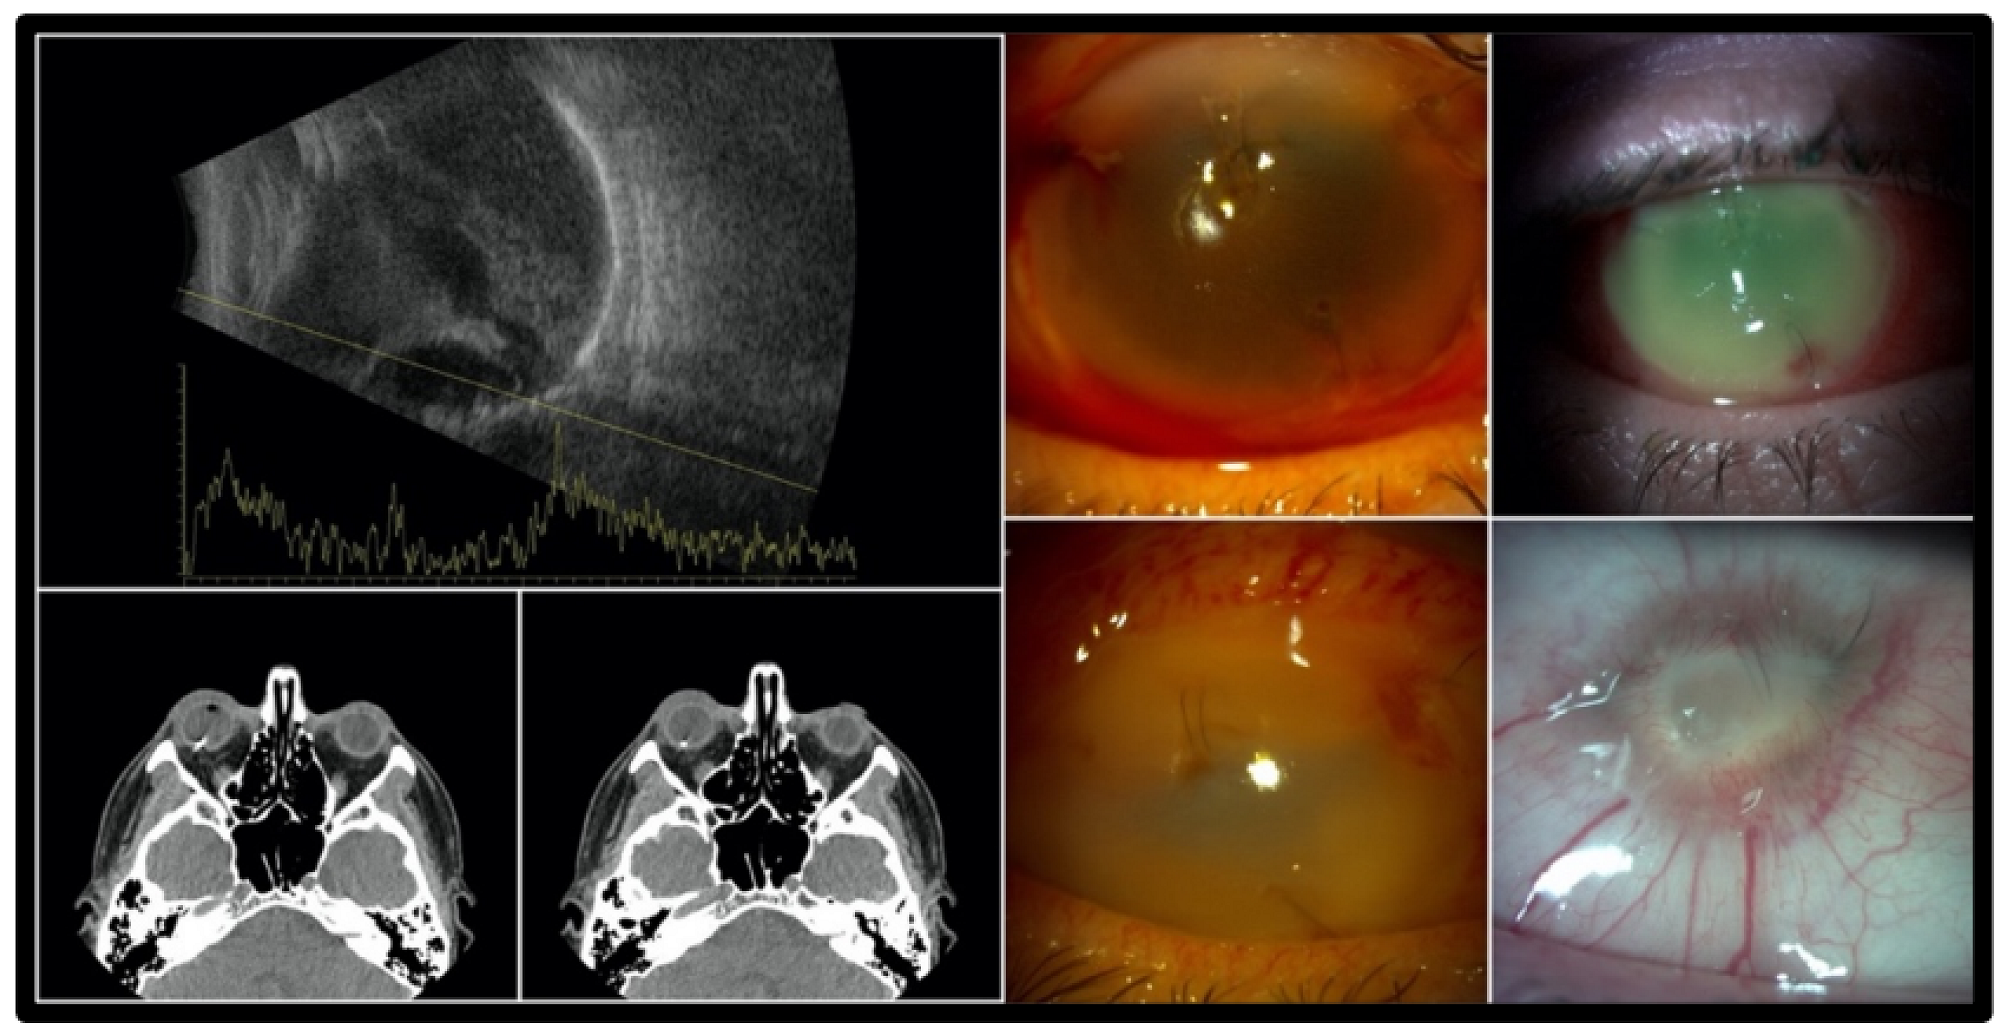

3.1. Clinical Presentation

3.2. Management